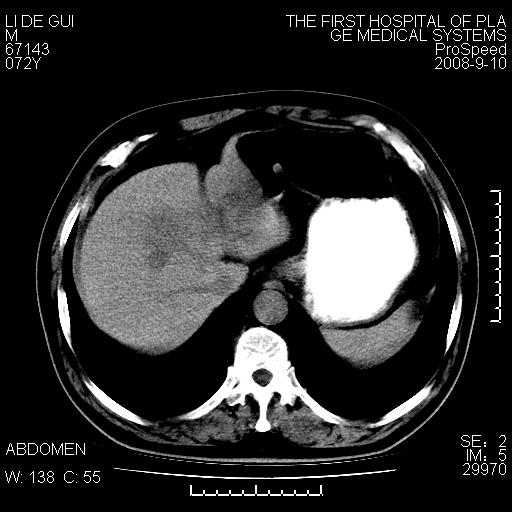

标题: CT17988:腹部肿块两年,肿块大小无变化,患者无不适,自我 [打印本页]

标题: CT17988:腹部肿块两年,肿块大小无变化,患者无不适,自我

胆囊占位性病变(黄色肉芽肿性胆囊炎?)。

考虑-----胆囊血肿机化或胆囊癌或腺肌增生症------增强

胆囊占位性病变,增强。

十二指肠的间质瘤